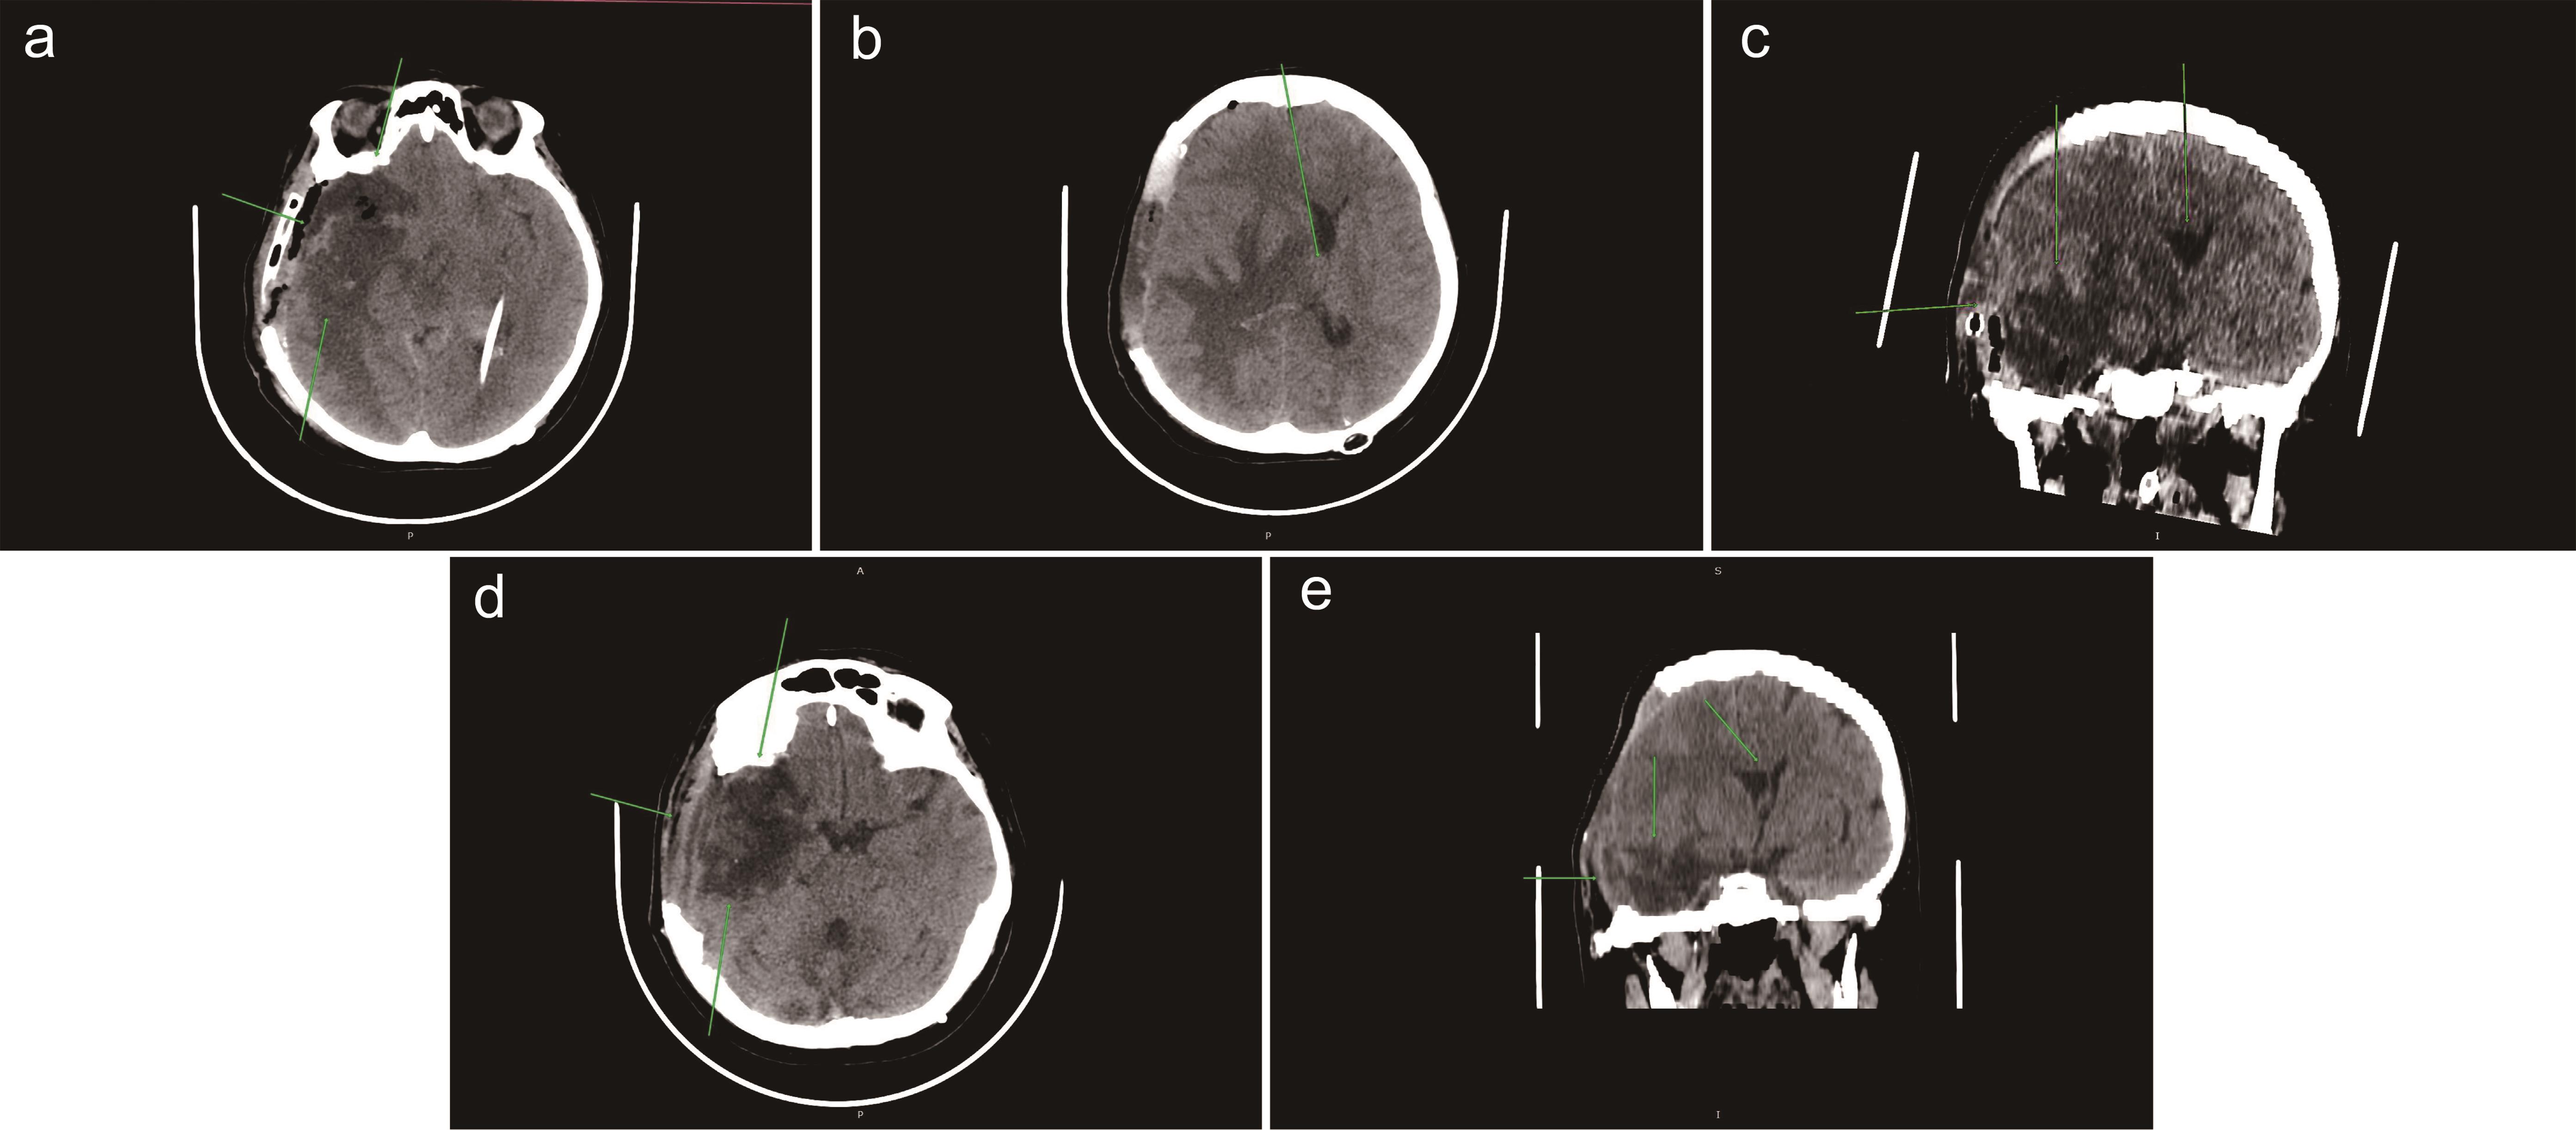

Fig. 3  Postoperative state after tumor resection in the right temporal lobe (March 5, 2022).

In the right temporal lobe, a pathological zone with unclear margins is identified, including a cyst (a), residual tumor (b), and a gliosis-affected area visible on T2-weighted image (T2WI) and fluid attenuated inversion recovery (FLAIR) sequences with surrounding perifocal edema (c) and signs of restricted diffusion on diffusion-weighted imaging (DWI) (d). In the region of the cerebellar vermis and right cerebellar hemisphere, a zone of cystic-gliotic changes is identified (e, f). Displacement of midline structures is also observed (f).